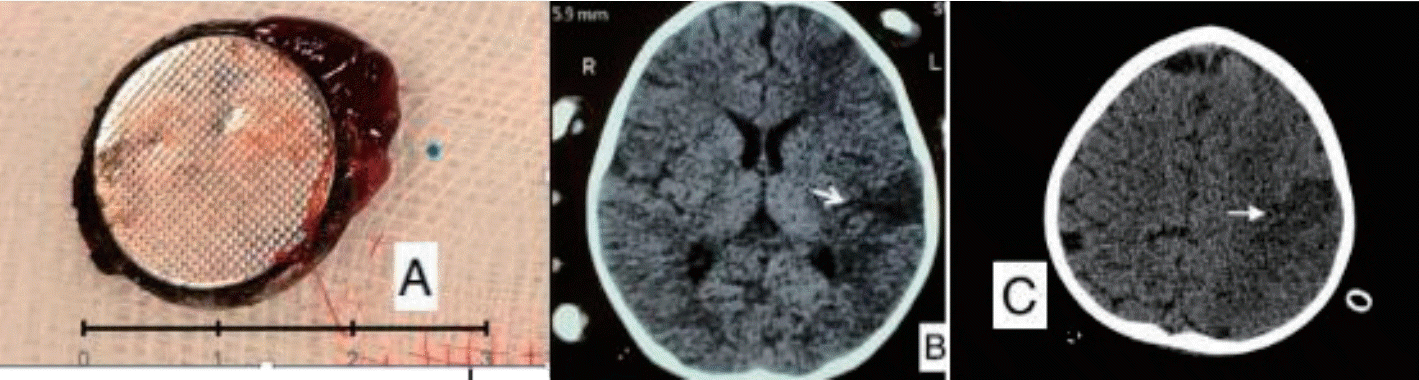

A previously well 18-month-old boy presented with 16 days history of poor feeding, fever and 2 episodes of clinically significant, well compensated upper gastrointestinal bleeding (UGIB) in the form of hematemesis and melena on day 10 and day 14 of illness respectively. He was transfused 2 units of packed red blood cells (PRBCs) elsewhere before presenting to us. On examination, the child was irritable, severely pale and had no splenomegaly. There was no history of witnessed foreign body ingestion. An urgent upper gastrointestinal endoscopy was performed after hemodynamic resuscitation which revealed an impacted foreign body in the upper esophagus with surrounding ulcerated mucosa (Fig. 1A). X-ray showed envisioned halo sign suggestive of BB (Fig. 1B). Computed tomography angiography (CTA) showed proximal left common carotid artery (CCA) pseudoaneurysm (4.9 mm×4 mm) in close proximity to BB suggestive of vascular fistula (Fig. 1C and D). Surgical consult was sought and BB removal was planned in operation theatre (OT) with cardiovascular and thoracic surgery back-up. Meanwhile, the child had another bout of massive UGIB requiring PRBC transfusions. After stabilization, the child was taken to OT and exploration was done via median sternotomy incision. Intraoperative findings included impacted BB in cervical esophagus and inflamed esophagus densely adhered to pretracheal fascia, left carotid sheath and prevertebral fascia. Intraoperative bleeding was seen at level of CCA, vascular control was ensured by using running sutures. BB was retrieved by intraoperative endoscopy by using grasping forceps. It was a lithium BB (20 mm×20 mm) (Fig. 2A). Esophagectomy with cervical esophagostomy, decompressive gastrostomy and feeding jejunostomy were done. Following surgery, feeding was established via jejunostomy. However, the child had right hemiparesis. CTA-head showed infarct in left parieto-temporal region involving middle and anterior cerebral artery territory (Fig. 2B and C). It was attributed to intraoperative compromised cerebral circulation due to probable clamping of branch of CCA while ensuring vascular control. Postoperative, child had fever, so antibiotics were upgraded from first-line (cefotaxime, amikacin and metronidazole) to piperacillin-tazobactum and teicoplanin. Blood culture grew Enterococcus fecalis sensitive to teicoplanin and child responded. Fortunately, hemiparesis has improved over the next one month and the child is on full enteral feeds and has a plan to restore anatomy after 3 months.

(A) Upper gastrointestinal endoscopy image showing an impacted foreign body (white arrow) in the esophagus with surrounding charred mucosa. (B) Halo sign on x-ray (anteroposterior view). (C) Computed tomography angiography (CTA; coronal section) showing the left common carotid artery (LCCA), a pseudoaneurysm (PA) (red arrow), and a button battery (BB) (yellow arrow). (D) CTA (sagittal section) showing the LCCA (white arrow), PA (red arrow), and BB (yellow arrow).